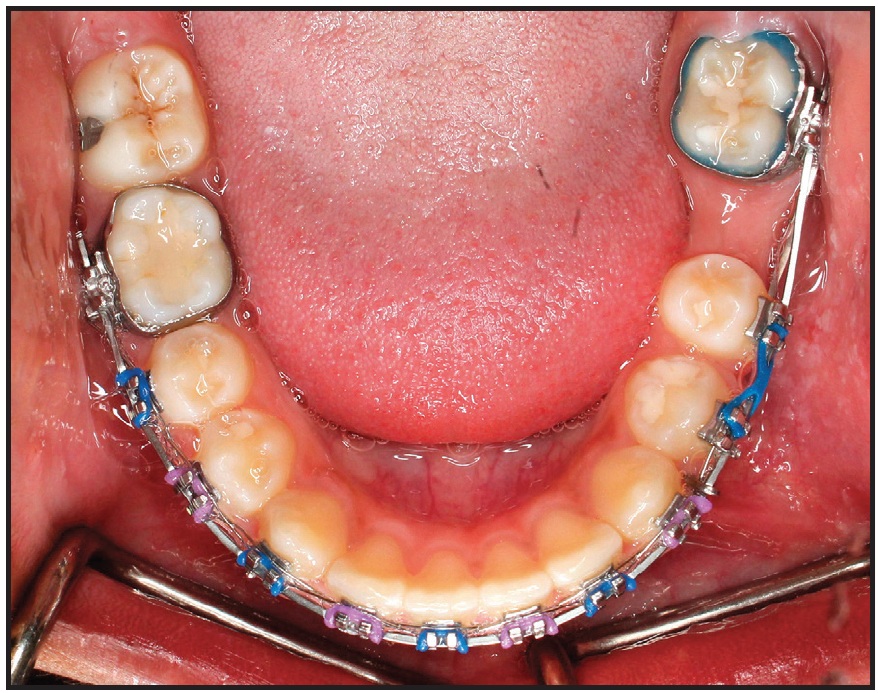

To further level and align the uprighted second molar with the rest of the lower arch, a continuous .016" x .022" nickel titanium archwire was placed. Three months later, an .019" x .025" stainless steel archwire was placed and a 1.8mm x 8mm mini-implant** was inserted interdentally between the lower left premolars. The lower left second-premolar bracket was removed, and bands were placed. A lower alginate impression was sent to the laboratory for fabrication of the previously described molar protraction appliance (Fig. 8).

Fig. 8 After 16 months of treatment, lower molar-protraction appliance cemented in place; stainless steel power arm splinted to mini-implant between lower left premolars and cinched in buccal premolar tube for indirect anchorage.

Every six weeks, the appliance was reactivated by attaching new elastomeric chain on both the buccal and lingual sides. The lower left second molar was mesialized in nine months, with only .5mm of anchorage loss of the second premolar (Fig. 9). The appliance was then removed, and a panoramic x-ray indicated that the movement was close to translation. At this point, the buccal segments were in an end-on Class II relationship. A fixed-functional appliance (Forsus Fatigue Resistant Device*) was then delivered to be worn for six months. After the anteroposterior discrepancy was corrected, finishing was carried out with .016" x .022" beta titanium archwires and light seating elastics.